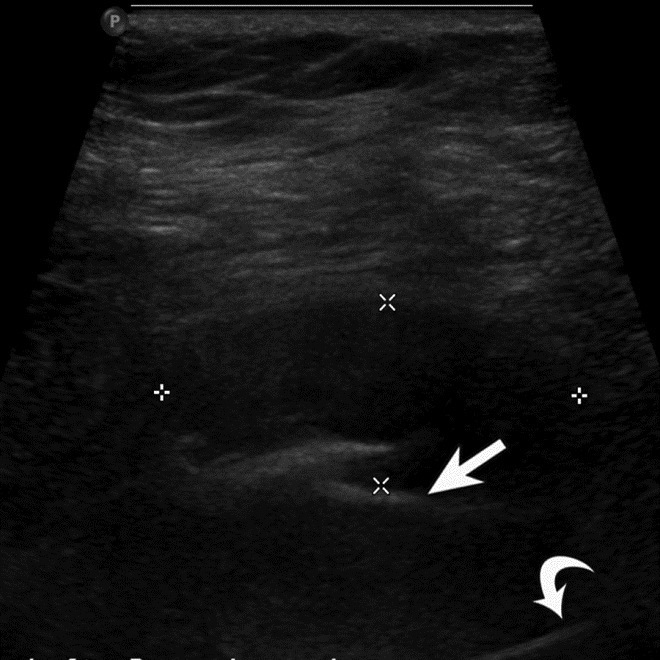

This technique can be used to evaluate for pseudotumor in metal-on-metal implants with rapid assessment of anterior, posterior, and lateral aspects of the hip to identify heterogeneous, hypoechoic masses with no or minimal intralesional vascularity on Doppler ultrasound (Figure 27) (Chen, 2011). It is also useful for evaluation of the rotator cuff in patients with prior cuff repair or proximal humerus fracture fixation (Figure 28), as well as for assessment of ankle tendons in patients with persistent pain following fracture fixation.